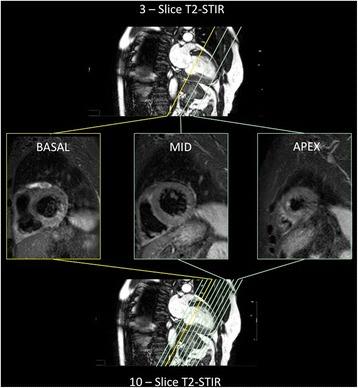

AAR measurement is useful when assessing the efficacy of reperfusion therapy and novel cardioprotective agents after myocardial infarction. Multi-slice (Typically 10-12) T2-STIR has been used widely for its measurement, typically with a short axis stack (SAX) covering the entire left ventricle, which can result in long acquisition times and multiple breath holds. This study sought to compare 3-slice T2-short-tau inversion recovery (T2- STIR) technique against conventional multi-slice T2-STIR technique for the assessment of area at risk (AAR).

CMR imaging was performed on 167 patients after successful primary percutaneous coronary intervention. 82 patients underwent a novel 3-slice SAX protocol and 85 patients underwent standard 10-slice SAX protocol. AAR was obtained by manual endocardial and epicardial contour mapping followed by a semi- automated selection of normal myocardium; the volume was expressed as mass (%) by two independent observers.